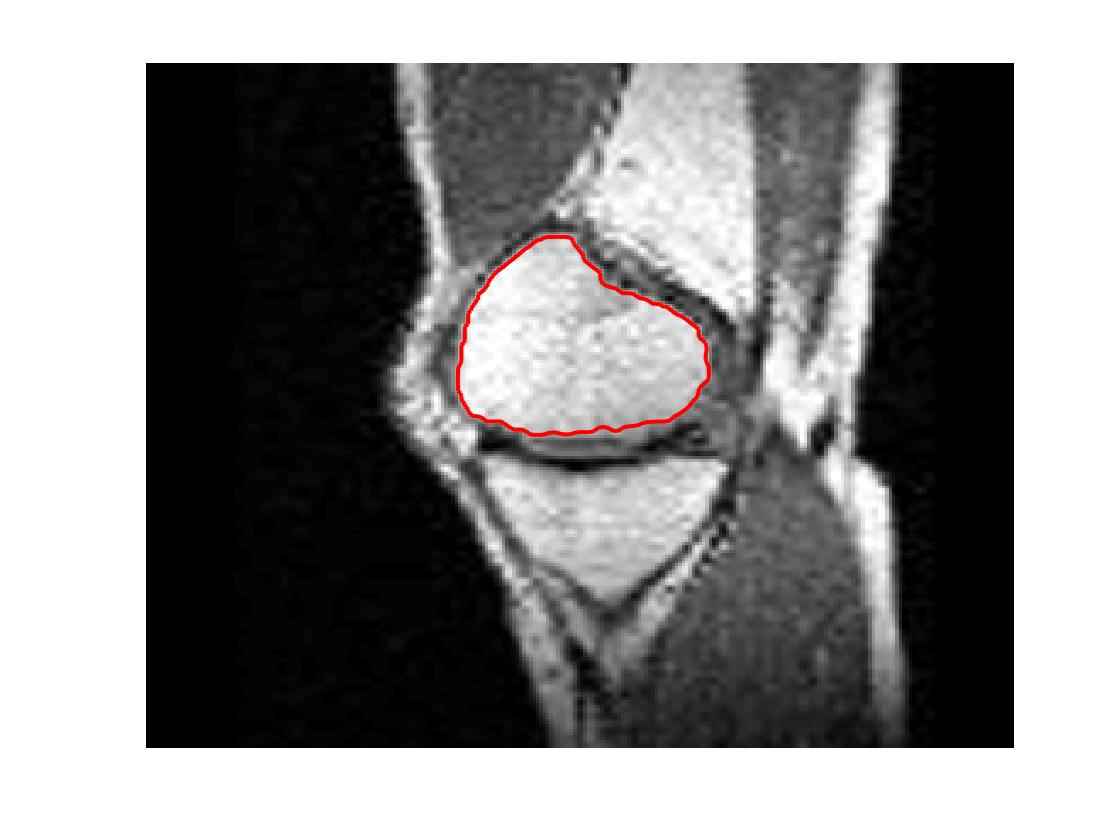

Four sets of test results are shown below. In Test 1 we compare models M1 – M6 to the proposed model M7 for two images which are hard to segment. The first is a CT scan from which we would like to segment the lower portion of the heart, the second is an MRI scan of a knee and we would like to segment the top of the Tibia. See Figure 9 for the test images and the marker sets used in the experiments. In Test 2 we will review the sensitivity of the proposed model to the main parameters. In Test 3 we will give several results achieved by the model using marker and anti-marker sets. In Test 4 we show the initialisation independence and marker independence of the Geodesic Model on real images.

Refer to captionRefer to captionRefer to captionRefer to caption

(i)                                 (ii)                                 (iii)                                 (iv)

Figure 9: Test 1 setting: (i) Image 1;  (ii) Image 1 with marker and anti-marker set shown in green and pink respectively;  (iii) Test Image 2; (iv) Image 2 with marker set shown.

Refer to caption

(a) M1 (Left to right:) Test Image 2 with markers (red) and anti-markers (blue), foreground segmentation and background segmentation (we used published software, no parameter choice required).

(b) M2 λ=1𝜆1\lambda=1, γ=15𝛾15\gamma=15.

(c) M3 λ=5𝜆5\lambda=5, θ=1𝜃1\theta=1.

(d) M4 λ=1/8𝜆18\lambda=1/8.

(e) M5 λ=1,γ=15,θ=110formulae-sequence𝜆1formulae-sequence𝛾15𝜃110\lambda=1,\gamma=15,\theta=\frac{1}{10}.

(f) M6 λ=15,θ=1formulae-sequence𝜆15𝜃1\lambda=15,\theta=1.

(g) M7 λ=10,θ=1formulae-sequence𝜆10𝜃1\lambda=10,\theta=1.

Figure 11: Visual comparison of M1 – M7 results for Test Image 2. M1 segmented part of the object, M2 – M4 failed to segment the object, M5, M6 and M7 correctly segmented the object.